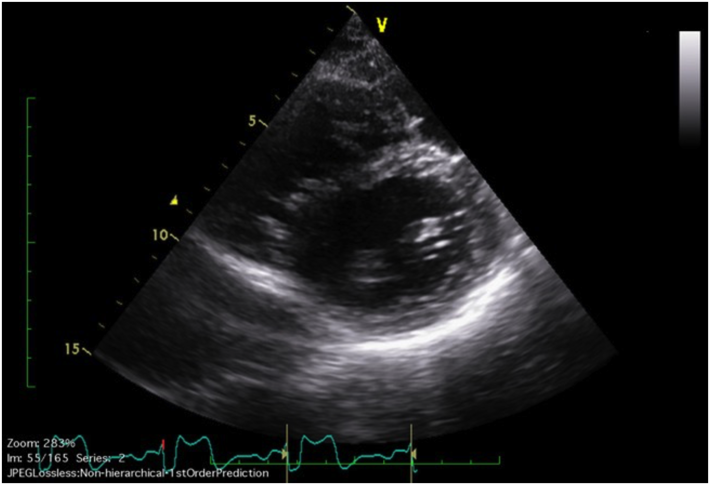

左単一冠動脈の拡張を伴い,SHOC2遺伝子異常が認められたNoonan症候群の1例A Case of Noonan Syndrome with the SHOC2 Mutation Complicated by Dilation of a Single Left Coronary Artery